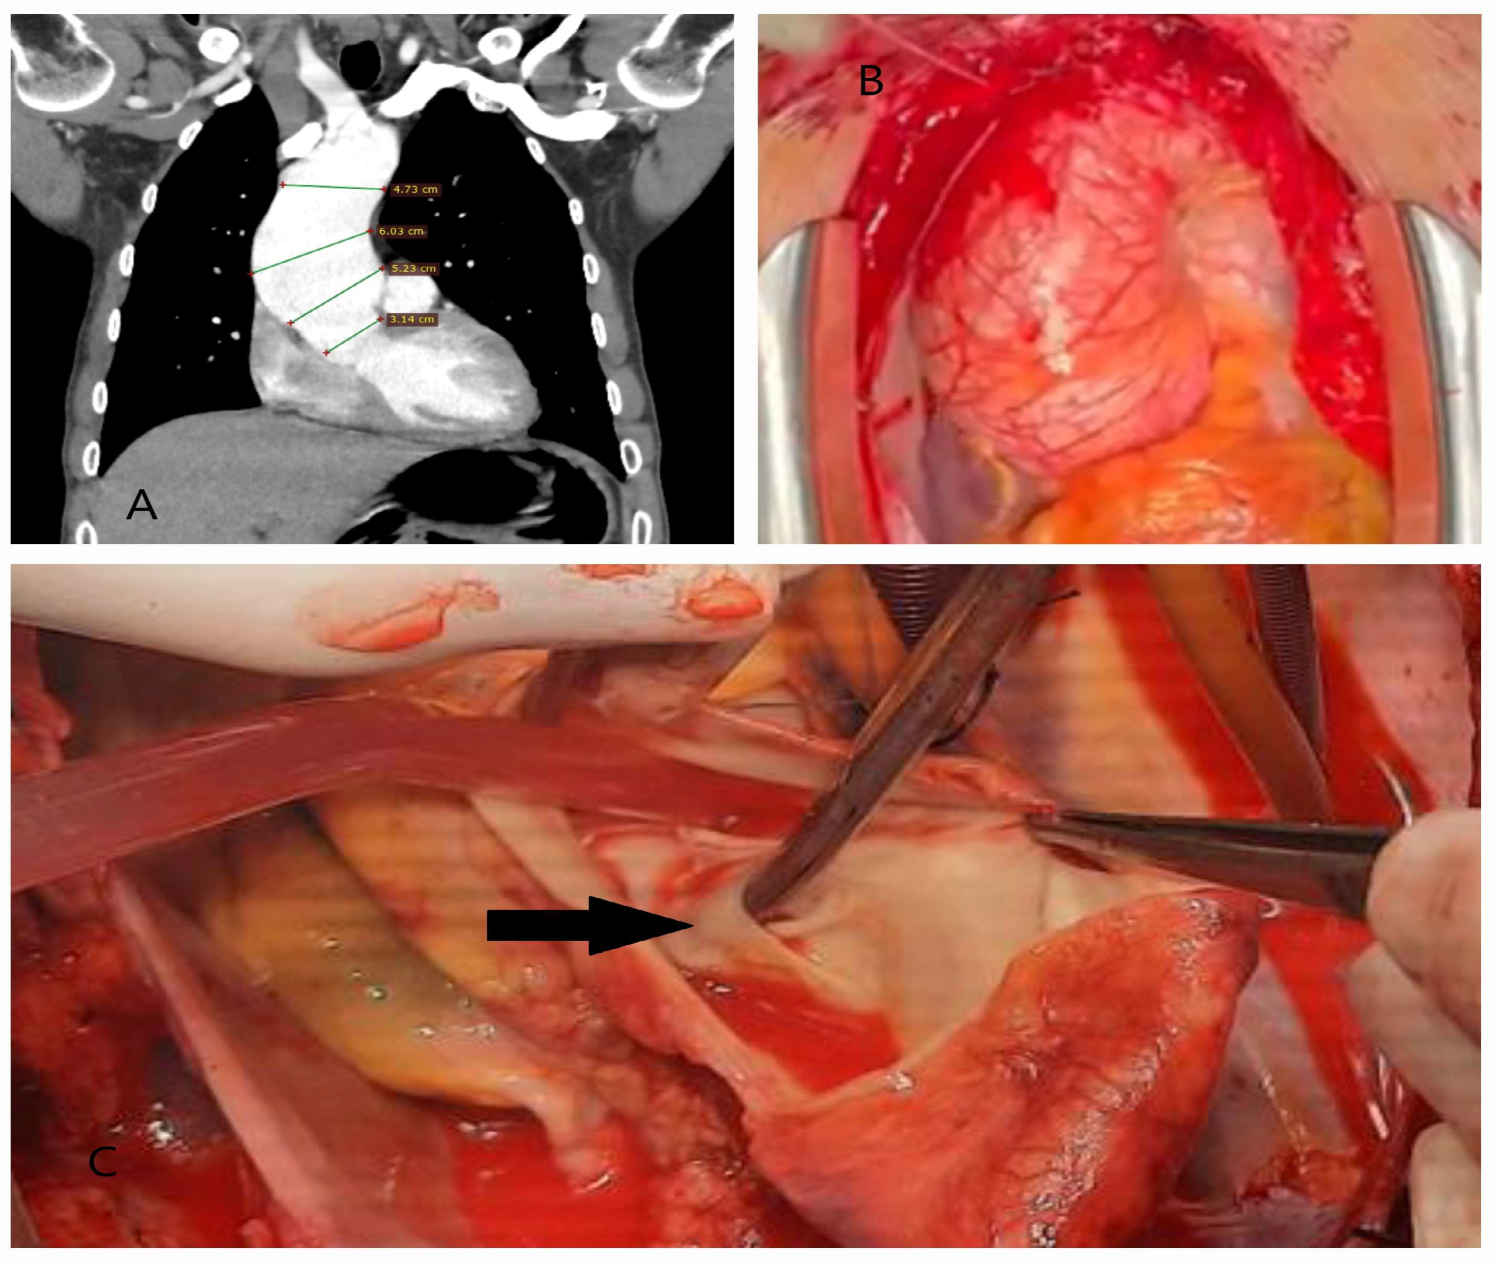

4.1. Dissection, Intramural Hematoma, and Penetrating Aortic Ulcer